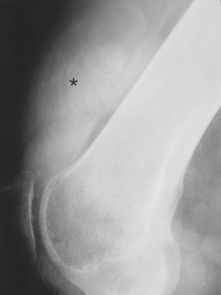

图14A -66岁男性,色素沉着绒毛结节性滑膜炎。照片显示胫骨近端的大的病变(箭头)延伸到关节面,类似巨细胞瘤。该病变代表着色素绒毛结节性滑膜炎的非典型大滑膜突出。

图14B -66岁男性,色素沉着绒毛结节性滑膜炎。膝侧位X线片显示髌上囊有异常密集的关节积液(星号)。